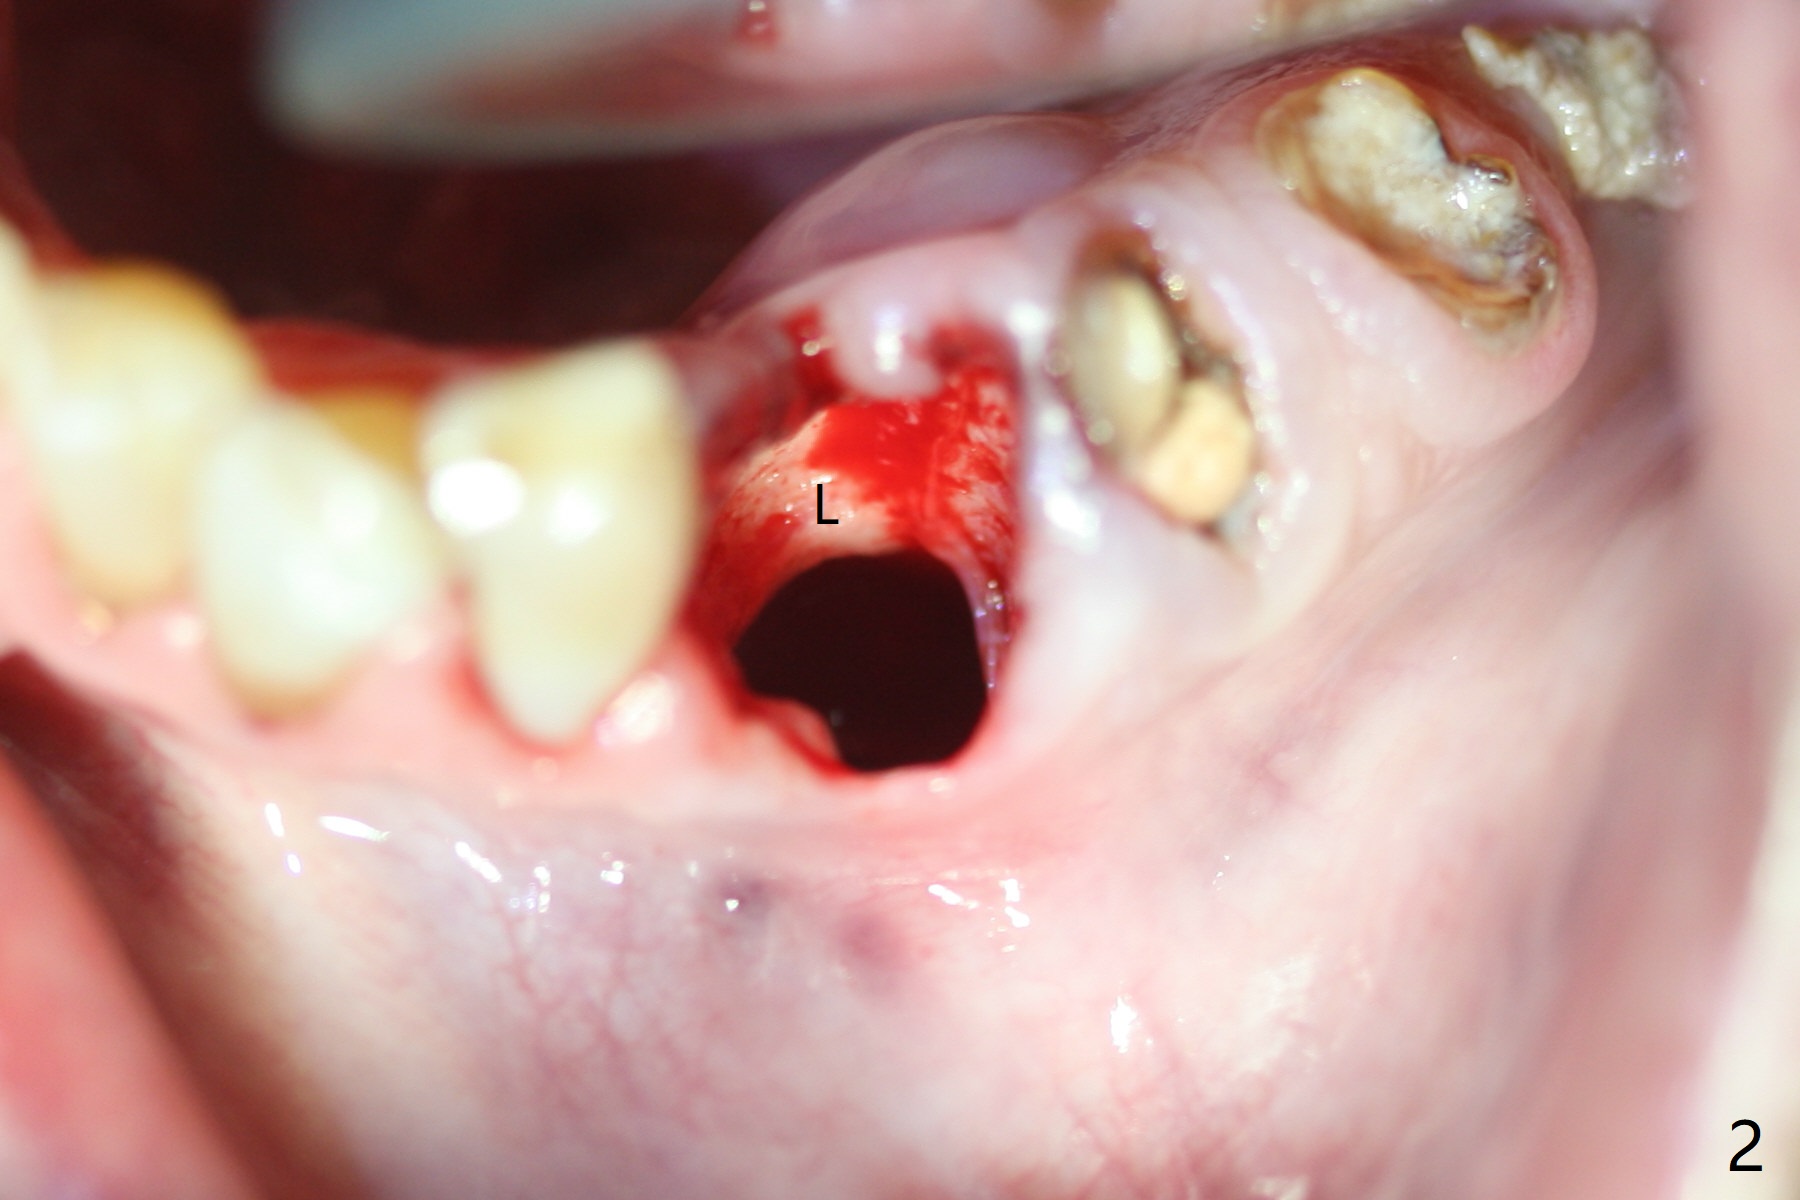

After removal of the split residual roots at #22 (Fig.1), the buccal wall is found to be defective, while the coronal portion of the lingual one (Fig.2 L) is confirmed to be more buccal than the apical portion. A vertical slot is made in the coronal portion of the lingual plate (Fig.3 *) in order to establish osteotomy lingual (Fig.4 O). The depth of the osteotomy in the apical native bone is 4.8 mm (Fig.5 CT coronal section). After the final drill (3 mm) is removed, a 3.8x16 mm implant is placed lingually for secure 2-pointed fixation (Fig.6,7, coronally: mesiolinguodistal; apically: in the native bone (Fig.9)). The essence of the lingual placement is the presence of a large buccal gap for Osteogen plug (Fig.8 yellow) and allograft (Fig.8 red, 9,10 (*)) for potential regeneration of the buccal plate. With bone graft and the overlying provisional (Fig.11 P), the buccal plate seems to have been established (*) 1 week postop. There is no obvious implant thread exposure 8 months postop (Fig.12). But the buccal plate is atrophic when the crown is cemented (~10 months postop, Fig.13).